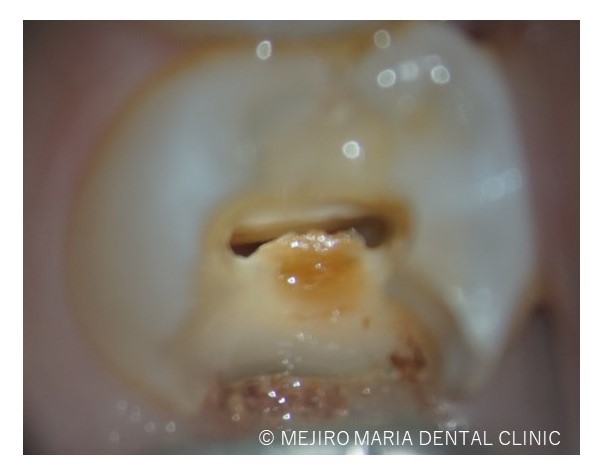

軟化象牙質を除去した際には、歯髄の血流は確認できませんでした。

診査の結果、右上5番の歯髄には歯髄生活反応は確認できず、歯髄壊死が起因となる根尖性歯周炎と診断しました。術前のレントゲン診査により、根尖が2つに分岐していることを確認できます。